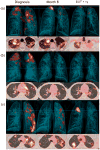

The absence of a gold standard to determine when antibiotics induce a sterilizing cure has confounded the development of new approaches to treat pulmonary tuberculosis (PTB). We detected positron emission tomography and computerized tomography (PET-CT) imaging response patterns consistent with active disease, along with the presence of Mycobacterium tuberculosis (MTB) mRNA in sputum and bronchoalveolar lavage samples, in a substantial proportion of adult, HIV-negative patients with PTB after a standard 6-month treatment plus 1 year follow-up, including patients with a durable cure and others who later developed recurrent disease. The presence of MTB mRNA in the context of nonresolving and intensifying lesions on PET-CT images might indicate ongoing transcription, suggesting that even apparently curative treatment for PTB may not eradicate all of the MTB bacteria in most patients. This suggests an important complementary role for the immune response in maintaining a disease-free state. Sterilizing drugs or host-directed therapies, and better treatment response markers, are probably needed for the successful development of improved and shortened PTB-treatment strategies.